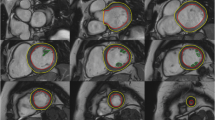

The majority of published articles used semi-automatic software for analysis of LV function and structure [10,11,12,13,14,15,16]. Short-axis images are most commonly analyzed on a per-slice basis, deriving LV mass and volume by applying the Simpson’s method (“stack of disks”) [17]. An example of LV contouring is shown in Fig. 1. Automated CMR analysis facilitated by machine learning is rapidly making inroads in LV volume and mass quantification [3]. The primary focus of early manuscripts has been on agreement between manual and automatic contouring [2]. However, to date, CMR variables for healthy cohorts have not been reported using machine learning methods.

Similar to the LV, analysis of the RV is usually performed on a per slice basis by manual contouring of the endocardial and epicardial borders. Volumes are calculated based on the Simpson’s method [17]. The RV volumes and mass are significantly affected by inclusion or exclusion of trabeculations and papillary muscles [27, 28]. For manual contouring, inclusion of trabeculations and papillary muscles as part of the RV volume will achieve higher reproducibility [9, 27, 28]. However, semiautomatic software is increasingly used for volumetric analysis, enabling automatic delineation of papillary muscles [29]. Therefore, normal values for both methods are provided. An example for RV contouring is shown in Fig. 1. Detailed recommendations for RV acquisitions and post processing have been published [9].